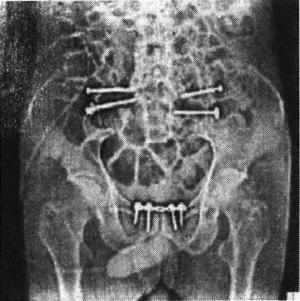

图13-61 骶髂关节螺钉固定术后X光片